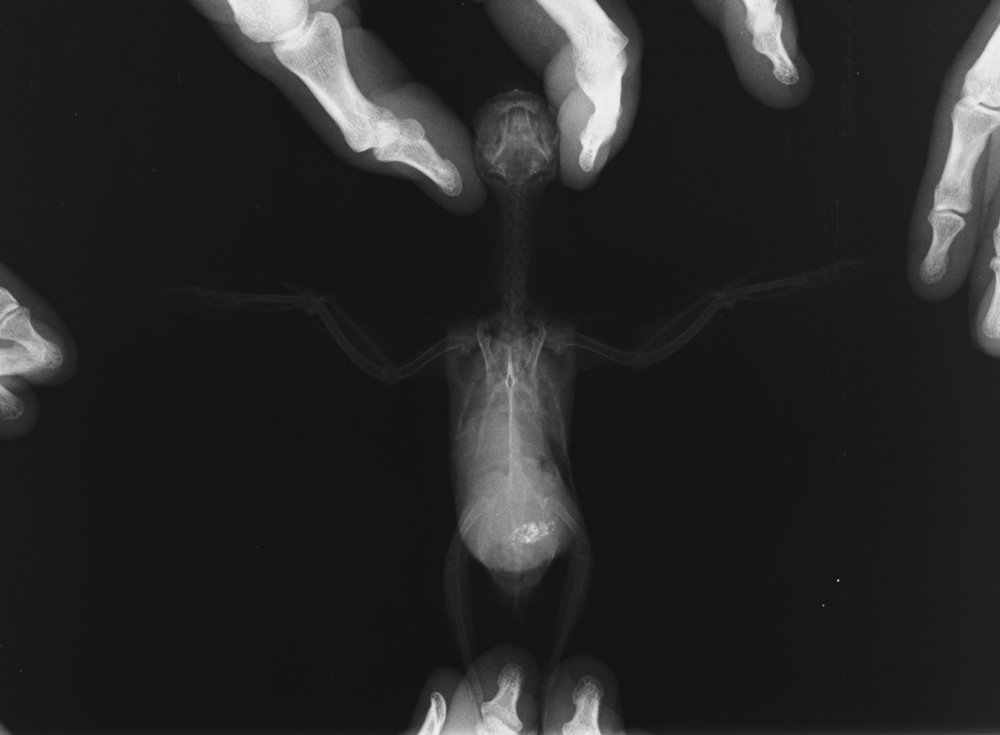

у птицы опухоль половой сферы -семенников, тут ренген нужен на спине и боку (как -см у меня в подписи), у меня как раз ваш случай живет (

Осмотрела попугая... в области семенников увеличение, зараза, дала о себе знать.. Поэтому ему что-то мешается. Еще 3 года назад на рентгене это было видно.

К врачу съездили.. 2 опухоли в районе легкого и одна в брюшной полости. Давит, поэтому одышка. Сдавлен пищевод..

Вот рентген(